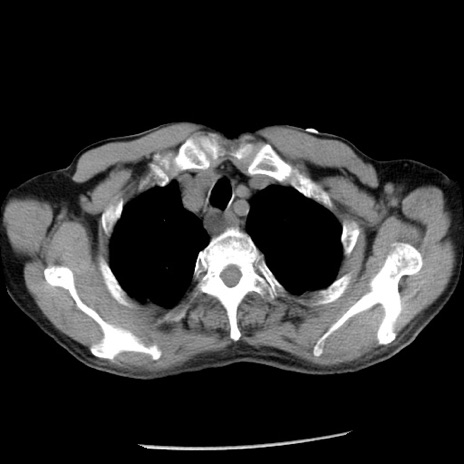

症例26(横断像)

【症例】80歳代男性

【主訴】嘔吐

【現病歴】昨晩2回嘔吐あり、今朝になっても嘔吐あり。来院。

【既往歴】胃潰瘍

【身体所見】意識清明、BT 37.6℃、BP 166/95mmHg、HR 100bpm、SpO2 97%、腹部:平坦・軟、腸蠕動音聴取良好、圧痛なし。

【データ】WBC 21900、CRP 1.46